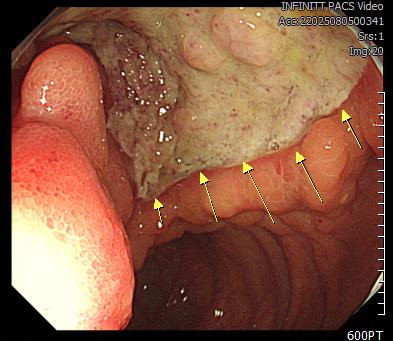

우 하복부에서 발견된 대장 베쳇트 병 (Behcet colitis) 1례

58세 된 남성으로서 최근 1개월 동안 소화가 안되고 배가 더부룩하다고 해서 내원하였다. 모친이 대장암을 ...